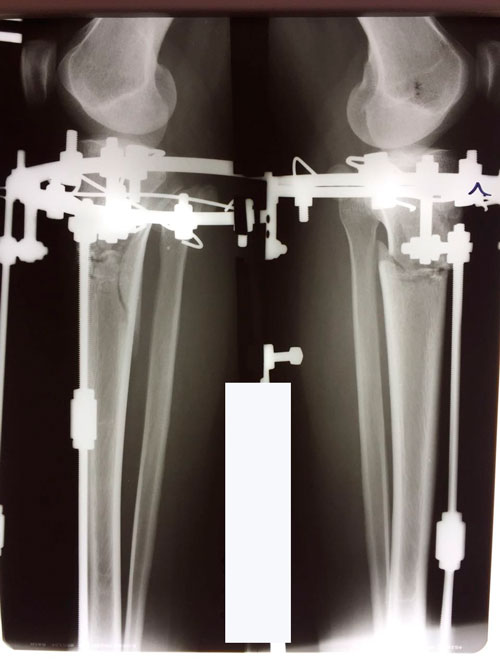

Исходник 28 лет.

Дата операции 17.03.2018г.

Дата снятия аппаратов 26.06.2018г.

Срок лечения 98 дней.